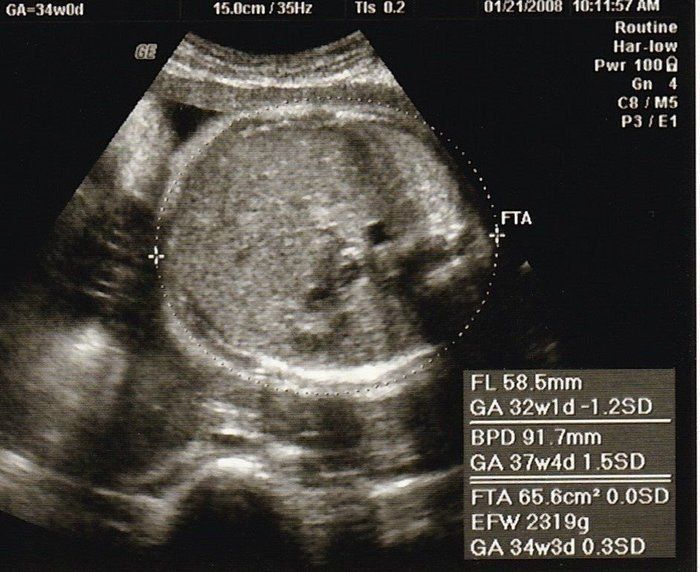

ベビオママさんの妊娠34週目のエコー写真 胎児が初めて2kg超え

一番白くはっきり写っているのは赤ちゃんの足の骨です。かなり太く、しっかりしてきました。小さく丸く写っているものがあったので、男の子であることも再確認できました。産院主催のお産の勉強会に参加して、いよいよ出産が近づいてきたと感じました。この時期には、夜中におなかが張ることが多くて、よく起きてしまいました。